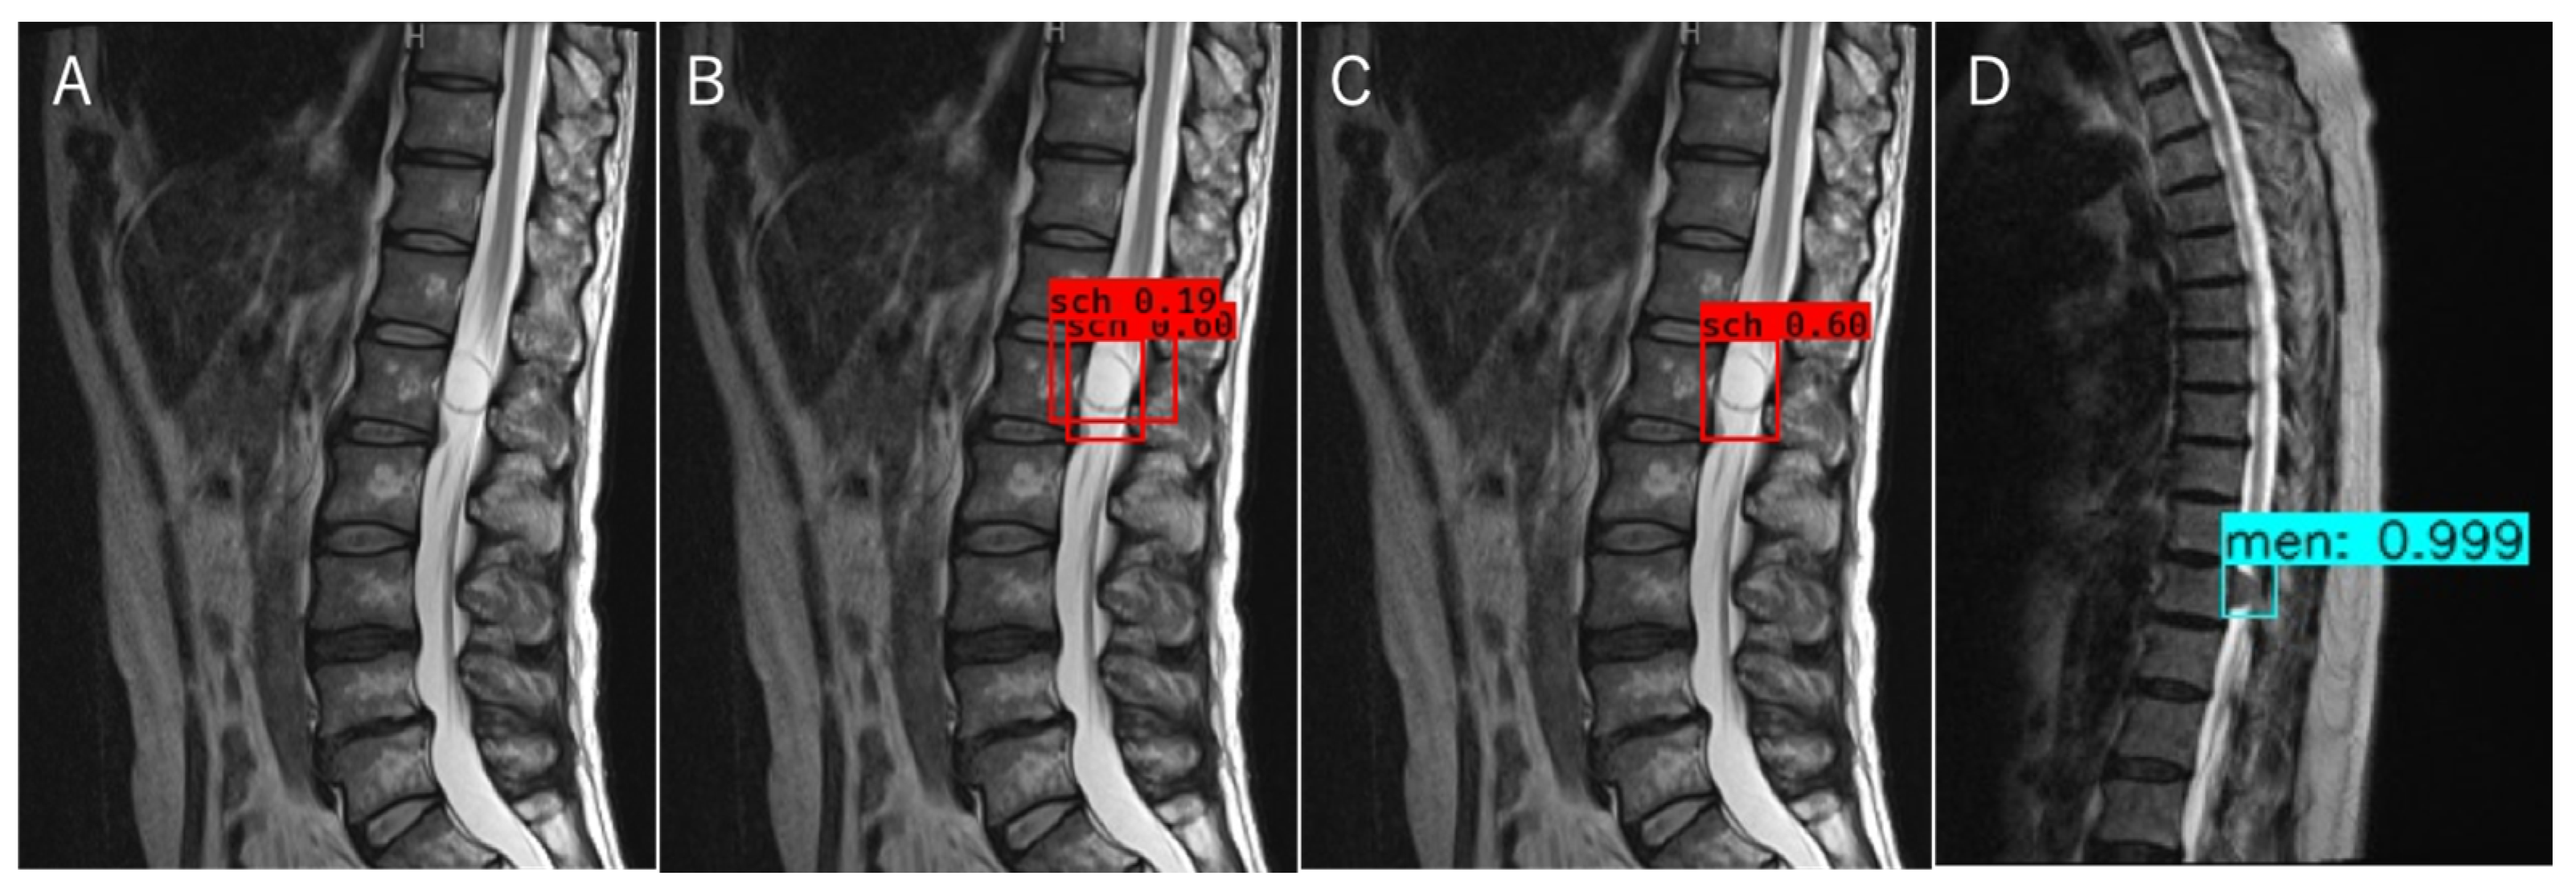

The object detection model was trained using the tumor locations and labels of the schwannomas and meningiomas as the training data. The optimal probability threshold was determined by performing a few trials. Figure 3A is an example of a T2WI MRI image of a schwannoma that was tested. A region with a probability exceeding the determined threshold was detected (Figure 3B). When multiple regions were detected during trained object detection, the region exhibiting the maximum probability was chosen (Figure 3C). For classification, we labeled the schwannomas red and meningiomas blue (Figure 3C,D), and trained the object detection model using T1W and T2W images separately. Object detection and classification achieved using T1WI and T2WI could identify the region with the highest probability achieved by using T1WI and T2WI separately (Figure 4). The object detection model was trained and validated using a computer equipped with a Quadro P6000 graphics processing unit (NVIDIA, Santa Clara, CA, USA), Xeon E5-2667 v4 3.2 GHz CPU (Intel, Santa Clara, CA, USA), and 64 GB of RAM.

Figure 4. Object detection and classification method using T1WI and T2WI. (A) The final region in T2W images; (B) The final region in T1W images; (C) The region with a higher probability shown in (A,B) was selected as the final region for T2WI and T1WI. T1WI, T1-weighted imaging; T2WI, T2-weighted imaging.